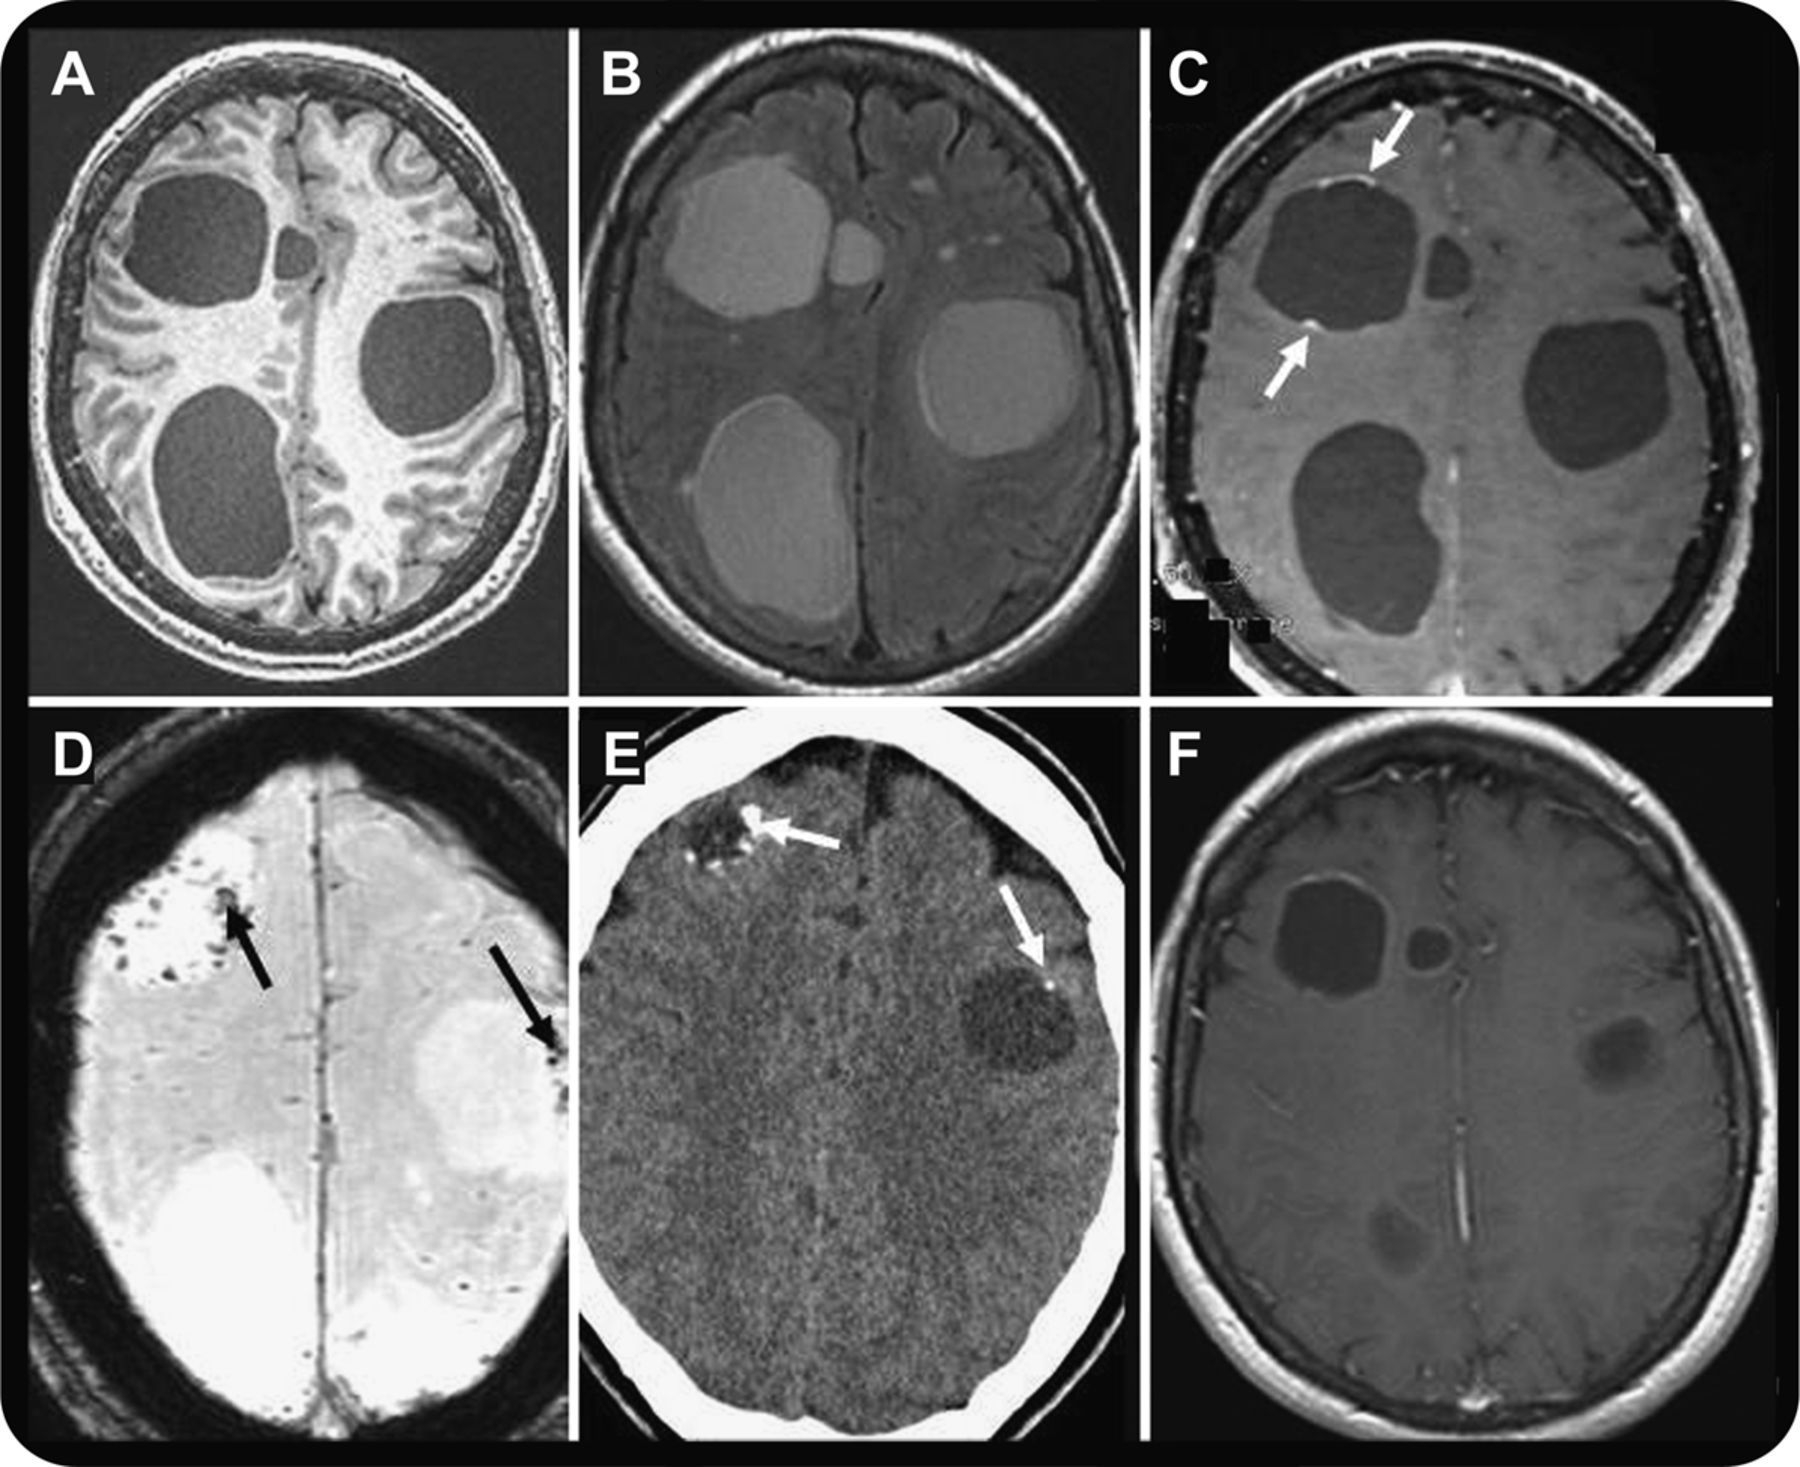

Breast cancer can virtually spread to any part of the body. The most commonly affected parts are: - brain - bones - lungs - liver Reference: https://www.cancer.net/cancer-types/breast-cancer-metastatic/introduction#:~:text=Metastatic%20breast%20cancer%20may%20spread,liver%2C%20lungs%2C%20and%20brain. Image via: https://n.neurology.org/content/79/24/2366